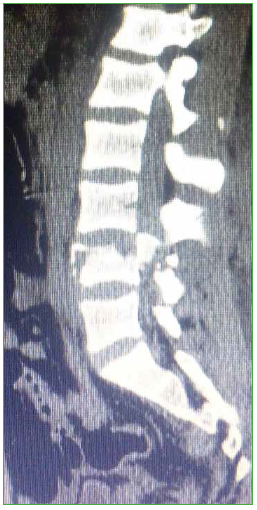

Figura 3. Caso 1. Tomografía

computarizada, corte sagital.

El paciente es trasladado al Servicio de Urgencia del hospital regional y, de allí, es derivado a nuestro centro, a través de su obra social. Ingresa, reactivo, lúcido (escala de Glasgow 15/15), con estabilidad hemodinámica y síndrome de cauda equina incompleto (grado B según el puntaje de la ASIA).19 Se solicitan radiografías y TC de columna cervical, torácica y lumbosacra. Se constata fractura vertebral lumbar baja con compromiso de la cuarta vértebra lumbar (L4), de tipo estallido, con retropulsión de un fragmento voluminoso del muro posterior en el canal, con impronta en el saco dural. La resonancia magnética no mostró una lesión del complejo ligamentario posterior, por lo que se interpreta, según la clasificación AO, como L4: A3, N3, M0 (Figuras 2 y 3). Sin deformidad en cifosis significativa y con un colapso vertebral inferior al 50%. Se constata una lesión hepática asociada, se lo somete a una laparotomía de urgencia y queda internado en la Unidad de Terapia Intensiva.